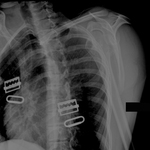

Joint dislocation

Scapular Y x-ray view showing an anterior fracture dislocation of the shoulder and fracture of the greater tuberosity